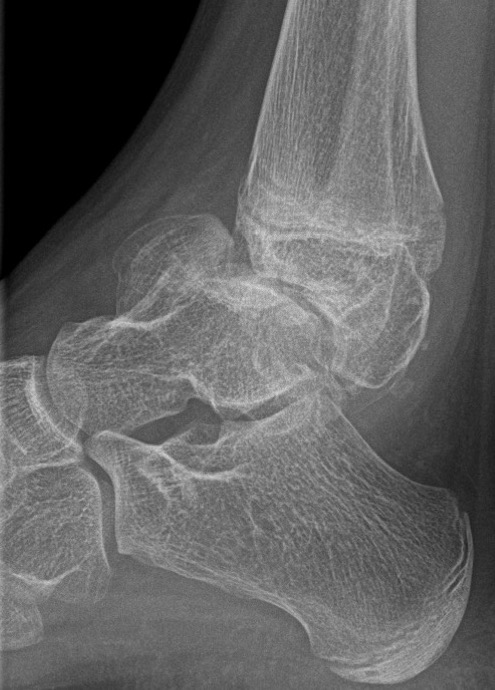

Ankle

Causes valgus deformity

- 19 patients with solitary osteochondroma of distal tibia or fibula

- cause plastic deformity and pronation deformity

- distal tibia more symptomatic than distal fibula

- 4/19 recurred

Appy-Fedida et al J Foot Ankle Surg 2017

- trans-fibular approach for worsening valgus deformity in 10 cases

- good functional outcomes

- recurrence in 1 case

- 7/10 developed tibiofibular synostosis